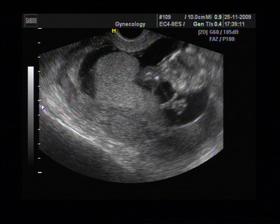

8/10 jsme se byli podívat u paní doktorky, zda testy nelhaly - a ono n e. Puclík měřil 0,37cm a co je důležité - srdíčko už funguje. Táta s Pepínem byli v ordinaci s námi, a když se na monitoru objevilo mimi, tak ho Pepíno pozdravil - udělal mu "ahoj" 🙂 oba nás to s Honzou dojalo. Další kontrola 22/10.